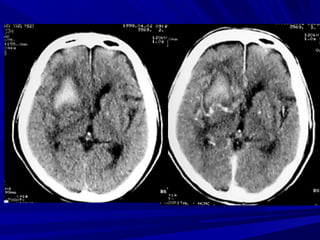

Phát hiện xuất huyếtPhát hiện xuất huyết

Xuất huyết là các vùng tăng đậm độ và có thể thấyXuất huyết là các vùng tăng đậm độ và có thể thấy

trong các bệnh lý:trong các bệnh lý:

Tụ máu ngoài màng cứng,Tụ máu ngoài màng cứng,

Tụ máu dưới màng cứngTụ máu dưới màng cứng

Xuất huyết màng nãoXuất huyết màng não

Xuất huyết não thấtXuất huyết não thất

Xuất huyết trong nãoXuất huyết trong não

Phân biệt hoá vôi và xuất huyết nhỏ vùng nhân nềnPhân biệt hoá vôi và xuất huyết nhỏ vùng nhân nền

Phân biệt xuất huyết cầu não với hình ảnh nhiễuPhân biệt xuất huyết cầu não với hình ảnh nhiễu